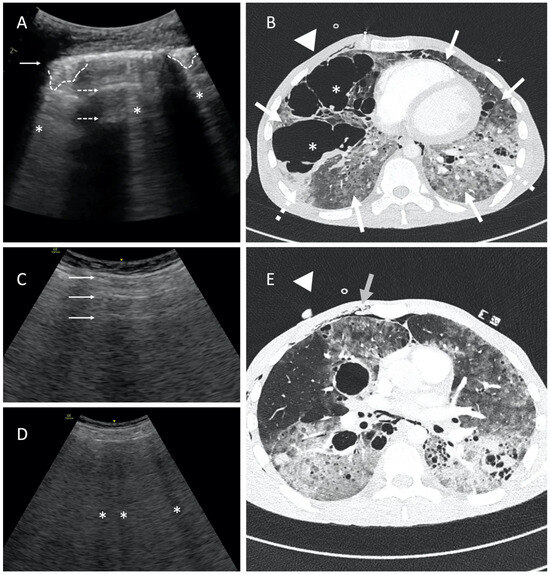

In hydropneumothorax, a typical lung point (Figure 1B; Video S1B) should be distinguished from a sign called the hydro-point (Figure 2; Video S2), where the air/fluid border appears as the interposition between an anechoic space and a non-sliding A-pattern [4]. The observed phenomenon resembles a curtain sign, but unlike the typical one, it can be seen in various areas of the chest wall, not only the base. Also, searching for the lung point can be difficult, time-consuming, or even impossible when the whole lung is collapsed.

Figure 2.

Point-of-care LUS of a 59-year-old smoker with COPD and severe ARDS. LUS was obtained with 1.8–6 MHz convex probe during vv-ECMO therapy and baby lung ventilation (Bilevel; FiO2 40%; PL10 cmH2O; PH 5 cmH2O; Vt~100–150 mL). Considering the LUS images obtained in the previous days (bilateral consolidations), the A-profile on the left side of chest wall was unusual. A careful assessment with LUS revealed the hydro-point, where a pleural effusion in the left pleural cavity coexisted with pneumothorax. Pneumothorax is present on the left side of the image with a blurred line of the parietal pleura (dashed arrow), and no horizontal reverberations developed at the air/tissue boundary. On the right side of the image, fluid in the pleural cavity (asterisk) and irregular, fragmented pleural line (solid arrow) with the subpleural consolidation (dashed line) can be observed. The contact point of both is called hydro-point (triangle), one of the non-typical LUS images confirming the presence of pneumothorax. This dynamic sign, occurring suddenly and transiently on the ultrasound image, can be seen in Video S2.